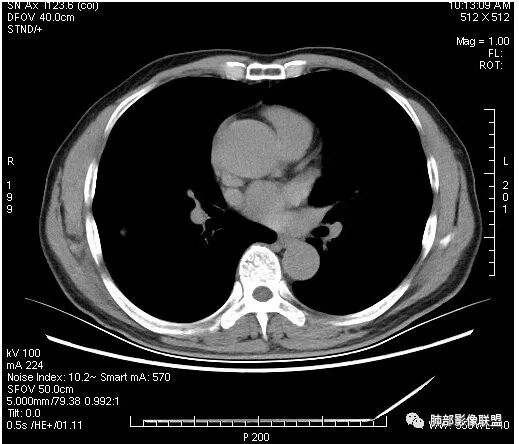

影像学改变:

1.右肺上叶后段类圆形结节影,密度不均,有坏死空洞,坏死比较彻底,内外壁都较清楚。

2.病灶有浅切迹,没有深分叶,毛刺大多细长且柔软。

3.可见棘状突起及胸膜牵拉,但未见胸膜凹陷。

什么意思?结节影有牵拉的动作,但似乎“出工不出力”,收缩力羸弱!

4.病灶轻到中度强化。病灶内血管走行较完好,病灶旁血管局部显示粗大。

5.支气管关系不确定。

6.灶周见小结节影(卫星灶),边界不甚清晰。